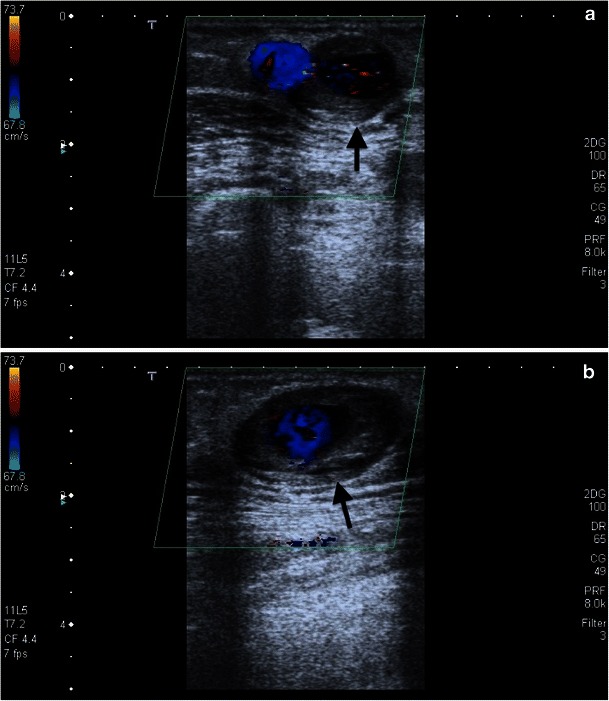

Fig. 21.

a, b. An aneurysma spurium is shown on duplex sonography in an area of palpable resistance laterally on the middle forearm in this 69-year-old female patient (black arrow). The aneurysm neck is 2 mm wide